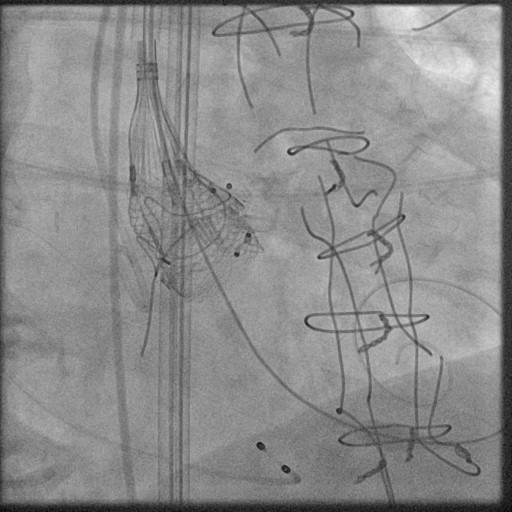

After creating an artero-venous loop between a transeptal and an arterial system, two vascular plugs (AVP III 10×5 and AVP III 8×4 ) were positioned and released, with their final position checked at TEE.

After one month, valve-in-valve TAVI using a Lotus 23 mm valve was performed. The use of a fully repositionable device was helpful to check final gradients before final valve release and obtain the best final position.